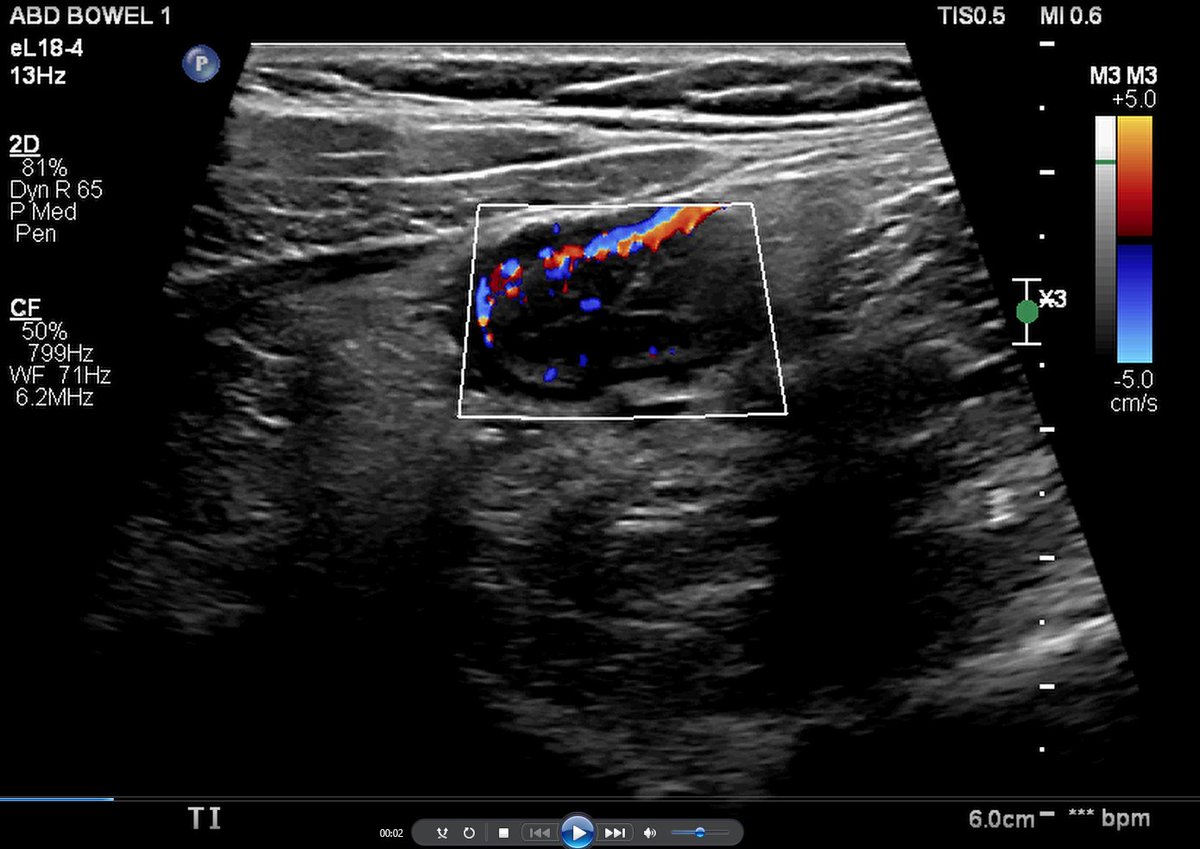

Hey Cigna Healthcare - this is what your inappropriate denial of infliximab means for my patient. Severe BWT of the neo-TI with a markedly increase doppler signal on bowel ultrasound = 🔥🤕suffering! Please answer our messages to restart therapy ASAP #FightWithUs